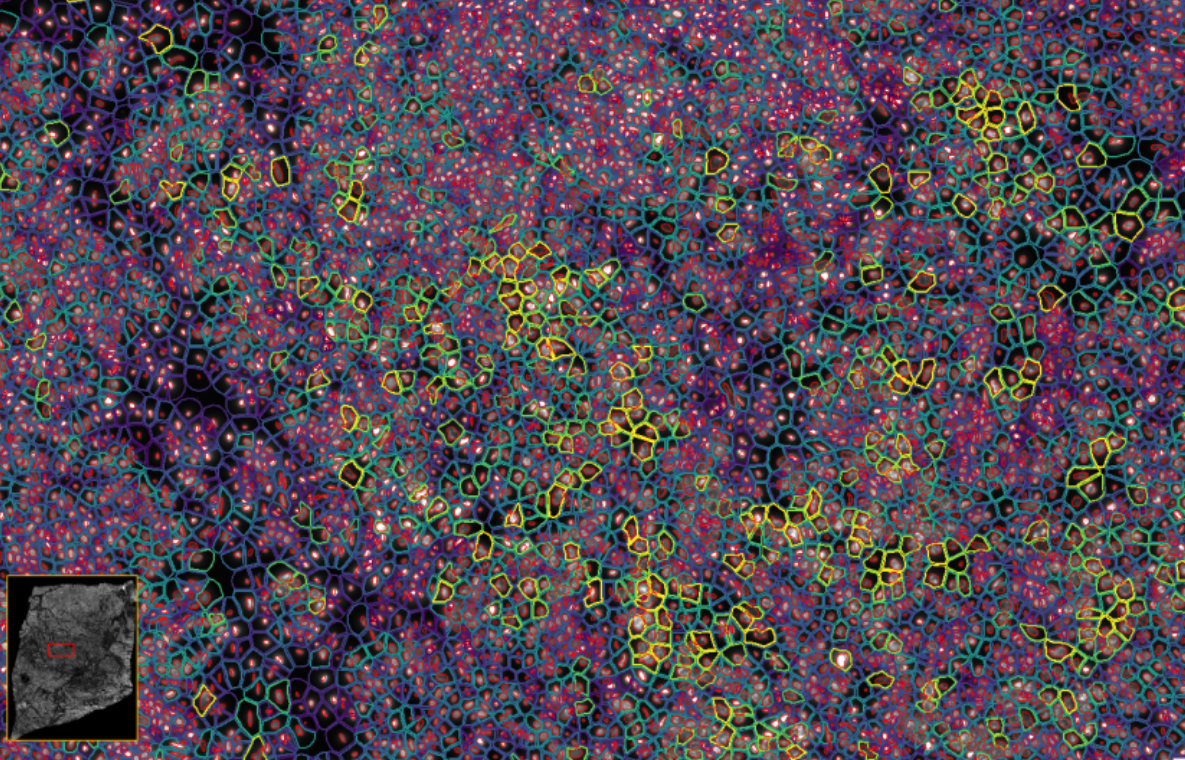

ͼ2£ºXeniumÊý¾Ý¸ÅÀÀ

ͼ3£ºXenium½«¹âÑ§ÌØµã½âÂëΪת¼±¾±í°×£¬²É¼¯²¢ÐγÉͼÏñ